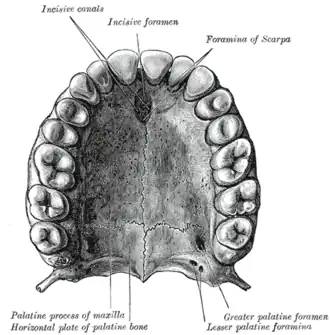

Inferior surface of maxilla. The bony palate and alveolar arch. (Palatine process labeled at bottom right.) | |

Inferior surface of maxilla. | |

When the two maxillae are articulated, a funnel-shaped opening, the incisive foramen, is seen in the middle line, immediately behind the incisor teeth.

In this opening the orifices of two lateral canals are visible; they are named the incisive canals or foramina of Stenson; through each of them passes the terminal branch of the descending palatine artery and the nasopalatine nerve.

On the under surface of the palatine process, a delicate linear suture, well seen in young skulls, may sometimes be noticed extending laterally and forward on either side from the incisive foramen to the interval between the lateral incisor and the canine tooth.

Occasionally two additional canals are present in the middle line; they are termed the foramina of Scarpa, and when present transmit the nasopalatine nerves, the left passing through the anterior, and the right through the posterior canal.